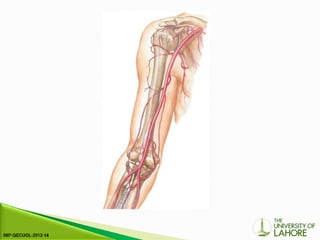

⦁ The subclavian arteries arise from the brachiocephalic trunk

on the right (Fig. 4-5) and directly from the arch of the aorta

on the left; however, there is considerable normal variation in

the patterns of their origination.

⦁ The origin of the right subclavian artery can be examined

behind the right sternoclavicular joint, where the

brachiocephalic trunk divides into the right common carotid

artery and the right subclavian artery.

⦁ The origin of the left subclavian artery from the aortic arch

cannot be demonstrated, although the more distal segments

can be seen as on the right side. The subclavian artery on

each side runs from its point of origin to the outer border of

the first rib where it becomes the axillary artery; the

subclavian vein lies in front of the artery.

⦁ In individuals with a cervical rib, the subclavian artery is

displaced cranially and anteriorly.

⦁ The main branches of the subclavian artery are the vertebral

arteries, the thyrocervical trunk, the internal thoracic

(mammary) artery and the costocervical trunk.

⦁ The axillary artery runs from the lateral border of the first rib

to the outer, inferior margin of the pectoralis major muscle.

⦁ The brachial artery passes down the medial aspect of the

upper arm to the cubital fossa and in joint space it divides

into the radial and ulnar arteries; the point of division

sometimes lies higher in the upper arm.